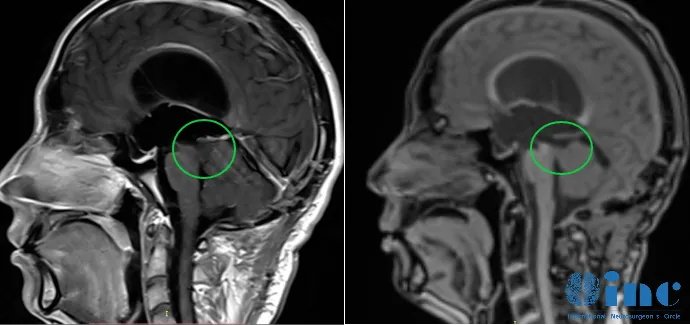

”中脑顶盖局部情况很好。我没有看到肿瘤复发,脑干的形态很好,肿瘤的低增殖率可能让我们至少在未来几年内预估不会有复发。我建议他定期进行核磁共振复查对比,也许每隔一年半进行一次,所以下一次是在2024年底。他可以把图像发给我们重新评估。“

术后4年,峥峥肿瘤未复发,如今的他已经脱离了稚嫩,成为了爸爸,新的角色,人生也重新开启。而成为爷爷奶奶的峥峥父母也万分感激,他们未曾想到,峥峥不仅安全全切了“人类禁区”脑干部位的胶质瘤,手术完之后还拥有的美好的爱情和幸福的家庭。